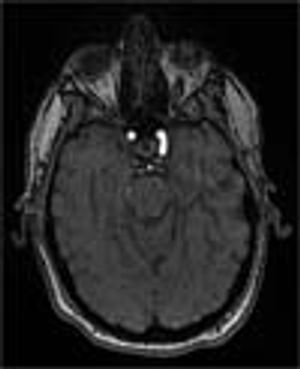

A 43-year-old white man presented to the emergency department with dyspnea, abdominal bloating, fever with chills, night sweats, decreased oral intake, and myalgia of 1 week's duration. He was found to have heart failure caused by systolic dysfunction. Viral myocarditis was the presumptive diagnosis after investigation for other causes.